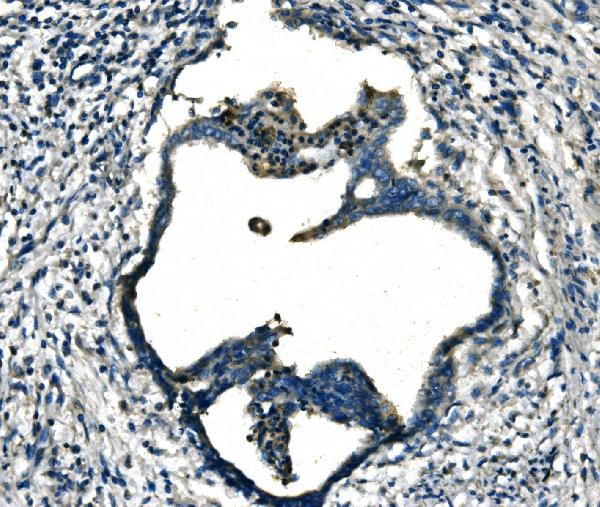

IHC (Immunohiostchemistry)

(Figure 2. IHC analysis of FGF4 using anti-FGF4 antibody (AAA126163).FGF4 was detected in a paraffin-embedded section of human cervical cancer tissue. Heat mediated antigen retrieval was performed in EDTA buffer (pH 8.0, epitope retrieval solution). The tissue section was blocked with 10% goat serum. The tissue section was then incubated with 2 ug/ml rabbit anti-FGF4 Antibody (AAA126163) overnight at 4 degree C. Peroxidase Conjugated Goat Anti-rabbit IgG was used as secondary antibody and incubated for 30 minutes at 37 degree C. The tissue section was developed using HRP Conjugated Rabbit IgG Super Vision Assay Kit with DAB as the chromogen.)